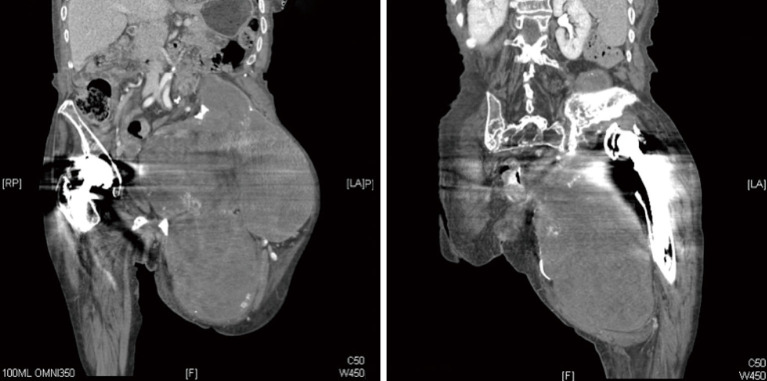

Background: The formation of destructive pseudotumors is a well-documented, albeit rare, complication of total hip arthroplasties. They tend to be progressive and, if left untreated, can result in extensive periprosthetic bony destruction. The current case presents a large benign mass consistent with a pseudotumor on both imaging and intraoperative findings but histologic findings demonstrating chronic hematoma.

Case description: An 86-year-old female with a metal-on-polyethylene total hip presented with a massive pseudotumor accompanied by extensive bony lysis. Due to pain and chronic anemia, a palliative debulking procedure was undertaken as a palliative measure. At one year follow-up, the patient reported significant pain relief and was able to ambulate safely with gait aids. Her hemoglobin stabilized post-operatively and ongoing transfusions were not required. Final pathology was not supportive of particle disease despite this being the leading diagnosis. Microscopic sections showed tissue mostly composed of fibrin and blood with multiple foci of calcification and reactive papillary endothelial hyperplasia which can be seen in chronic hematomas.

Conclusions: This case presents the diagnostic dilemma of a large benign mass consistent with a pseudotumor on both imaging and intraoperative findings but histologic findings consistent with a chronic hematoma. It highlights the importance of close follow-up and early intervention when periprosthetic osteolysis is detected.